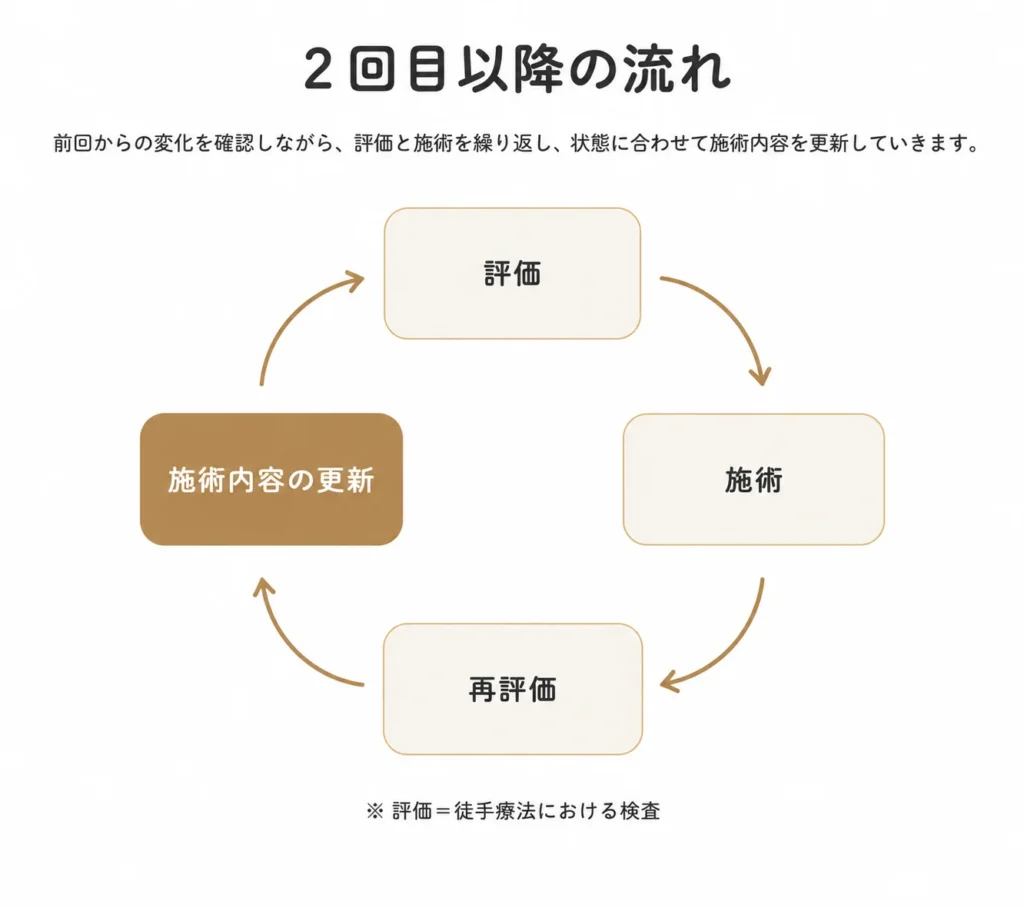

施術の流れ

症状箇所は同じでも、その理由はお一人おひとり異なります。

整体よしかでは、評価・施術・再評価・説明を大切にしています。